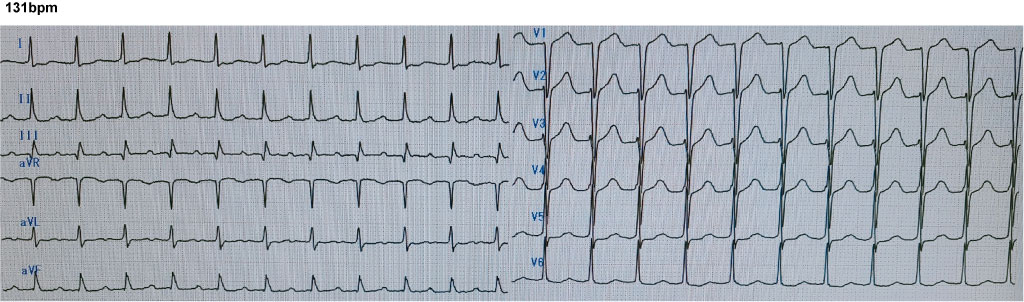

症例259

# 発作性上室性頻拍

男性。心筋梗塞既往。ペースメーカー留置。2週前から頻脈。本日、人間ドック。1週後、アブレーション予定。

<安静時心電図>